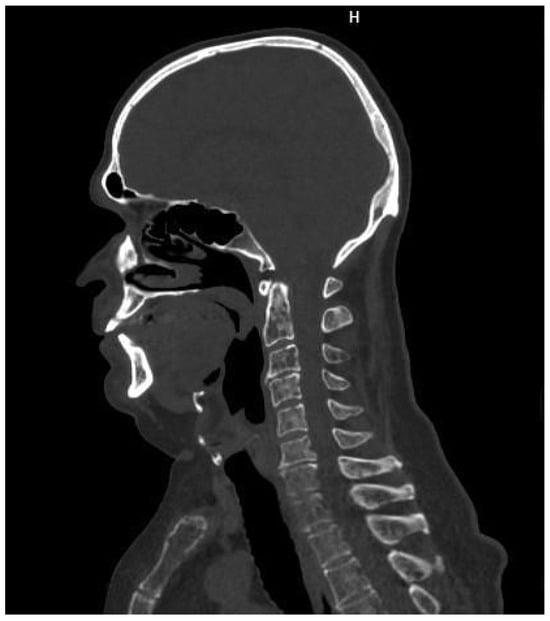

The presence of one or more sites of osteolytic bone destruction, at least 5 mm or greater in size, fulfills the criteria of bone disease in MM (CRAB), and therefore makes it necessary to initiate treatment (Figure 1, Figure 2 and Figure 3). In the case of smaller suspicious lesions seen in WBLDCT, they should be imaged within 3–6 months with CT or MRI to avoid overinterpretation [21,22].

Figure 2. A 63-year-old man with lytic lesions on the cervical spine, shown in whole-body low-dose computed tomography. Source: Radiological Diagnostics Center, The National Institute of Medicine of the Ministry of Interior and Administration, Warsaw, Poland.